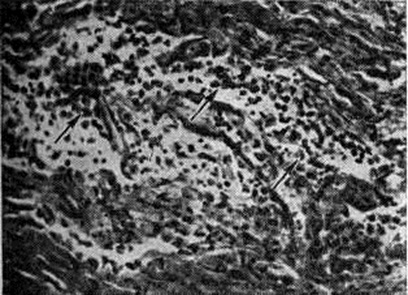

Рис. 2.

Микропрепарат зрительного нерва при полиневрите: инфильтрат в очаге демиелинизации, содержащий лимфоциты (1) и макрофаги (2); окраска гематоксилинэозином; ×400.